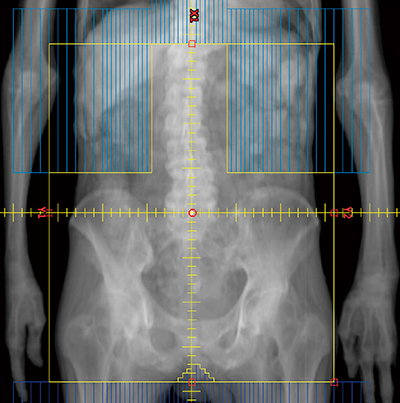

痛みの責任病巣が画像で特定できない肋骨転移には,治療計画装置は用いず,触診で照射野を設定して電子線照射を行っている。仰臥位になれない患者でも,側臥位で同様に電子線照射を行っている(図2)。

何箇所もの痛みに悩まされている患者であっても,例えば1日1部位ずつ単回照射を行えば,1週間で5部位を治療することも不可能ではない。TrueBeamの線量率は最高2400MU/sと高く,1門照射であれば30秒足らずで8Gyを照射することができ,仰臥位が容易でない患者でも放射線治療を完遂しやすくなった。

図2 肋骨転移の痛みで仰臥位になれない患者の放射線治療

びまん性骨転移で仰臥位が不可能であったが,触診で圧痛のある部位に×印を付け右側臥位のまま電子線を20Gy/5回照射したところ,放射線治療終了時には背部痛は消失し仰臥位が可能となった。